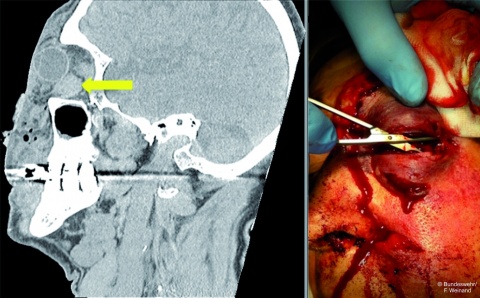

Akuter apikaler Abszess

er akute apikale Abszess stellt den schwersten endodontischen Notfall dar, da er mit massiven Einschränkungen des Allgemeinzustandes einhergehen kann und in der Regel eine Verwendung im aktiven Einsatz ausschließt (Abb. 5a & 5b).

Die Therapie besteht in der Drainage, die zumeist über die Trepanationsöffnung erreicht werden kann. Entleert sich trotz fluktuierender Schwellung in der Umschlagfalte kein Pus, kann vorsichtig mit einem feinen Instrument (ISO 10 – 15) kontrolliert werden, ob das Foramen ausreichend gängig ist. Entleert sich Pus, ist eine zusätzliche Inzision der Schwellung nicht notwendig, sie ist indiziert, wenn über den Wurzelkanal keine Drainage erreicht wird (Abb. 6). Der Wurzelkanal wird möglichst umgehend präpariert und sorgfältig desinfiziert, um die Keimzahl im Wurzelkanal schnell drastisch zu reduzieren. Ein Offenlassen des Zahnes ist kontraproduktiv und sollte nach Möglichkeit vermieden werden.